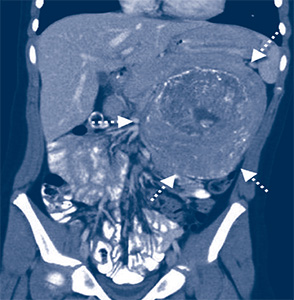

CT-Bilder eines Neuroblastoms bei einem 7-jährigen Mädchen

In Deutschland erkranken jährlich etwa 150 Kinder neu an einem Neuroblastom. Fast 90% der Patienten sind jünger als fünf Jahre. Am häufigsten betroffen sind Säuglinge vor dem ersten Lebensjahr. Neuroblastome entstehen aus entarteten unreifen Zellen des Nervensystems. Sie kommen am häufigsten im Nebennierenmark und im Bereich der Nervengeflechte beidseits der Wirbelsäule im Bauch, in der Brust oder im Halsbereich vor. Die Erkrankung weist sehr unterschiedliche Verläufe auf.

Eine Besonderheit der Neuroblastome ist, dass sie sich spontan zurückbilden oder zu gutartigen Tumoren ausreifen können. Diese Patienten können durchaus ausgedehnte Metastasen (Absiedlungen) vor allem in der Leber aufweisen, die rasch wachsen und durch die Verdrängung von Bauchorganen und der Lunge ein lebensbedrohliches Ausmaß erreichen. Diese Metastasen und auch der eigentliche Tumor bilden sich dann aber häufig spontan oder nach einer mild dosierten Chemotherapie zurück.

Besonders bei älteren Kindern jenseits des ersten Lebensjahres wachsen Neuroblastome allerdings oft sehr aggressiv und verbreiten sich schnell über das Blutoder das Lymphsystem im gesamten Körper. Es kommt zu schwer behandelbaren Metastasen, vorwiegend im Knochenmark und Knochen, in der Leber, der Haut und in entfernten Lymphknoten. Diese aggressive Form der Erkrankung führt auch heute noch trotz intensiver Behandlung häufig zum Tod der Patienten.